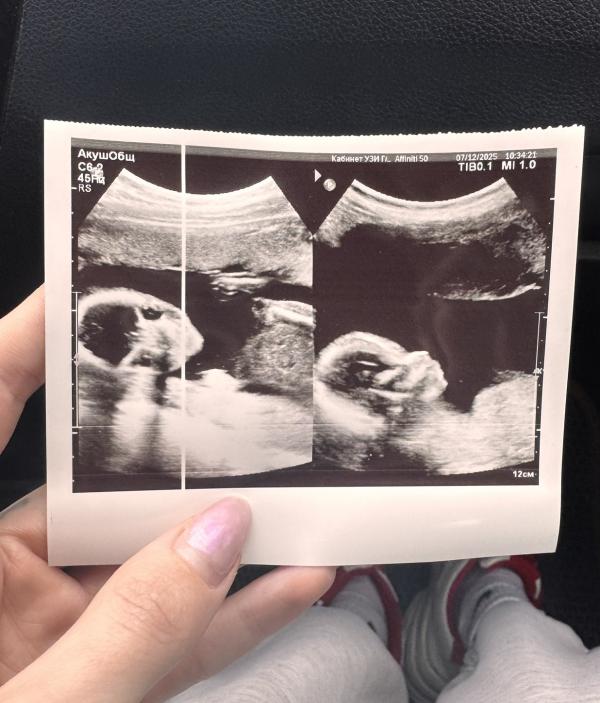

И так мы с сыном сходили на повторное узи, от которого будет отталкиваться гинеколог.

Малыш уже большой 😁😁 ну конечно 18 неделя, тут срок посчитали правильно, так же как и на скрининге. Никакого 296 грамм,230 сейчас весим. Но ноги длинные, сказали будет высоким, выше среднего роста. Длина шейки матки 49 мм, но это по животу, сказала, что конечно для точности надо трансвагинально смотреть, но она видит, что шейка хорошая длинна, а значит можно не лезть лишний раз.